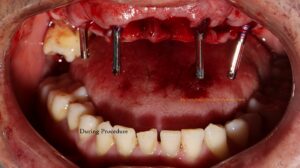

We then took measurements to create a diagnostic model, captured photographs, did scaling on lower arch and used virtual 3D planning to determine the optimal placement and size for the implants. On next day, following routine blood tests for the surgical procedure, we proceeded with the implant placement after removing his remaining upper teeth. Remarkably, on the same day, we were able to provide him with fixed temporary teeth. This 4-hour procedure was painless and uneventful, leaving him comfortable and with a full set of teeth.

Fig: Immediately after implant placement, Temporary immediate denture and Post- operative photograph immediately after surgery.